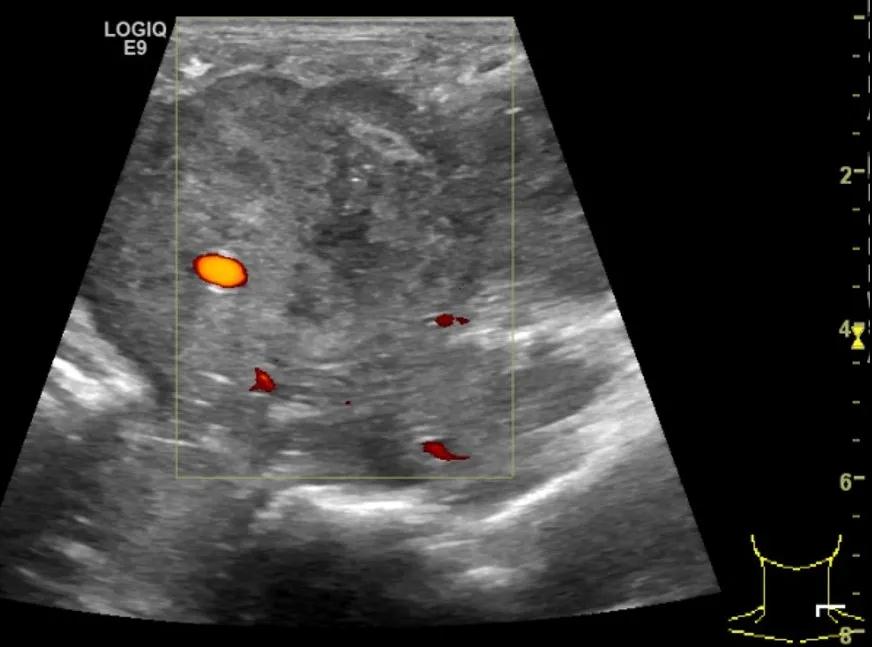

第二例是食管癌患者,术后半年余锁骨上固定淋巴结可触及肿大,疼痛非常明显,系统治疗后无缓解,患者希望通过局部处理缓解症状。造影显示强化信号明显,结节部分区域坏死,故主要针对强化区域从后向前的逐层的消融,皮下进行液体隔离减少烫伤。热消融后影像显示血流增强消失,弹性、硬度增高,一个月后复查显示充盈缺损,完全消融,疗效远超预期。

(病例2图例)